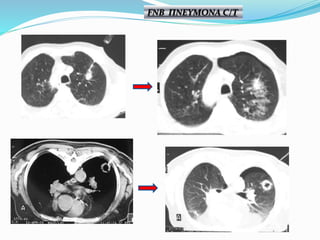

FNB ΠΝΕΥΜΟΝΑ C/T

Πνευμοθώρακας 11% Αιμορραγία 5% Αντίδρασηαπό το πνευμονογαστρικό <1% Τρώση μεσολοβίου < 1% Θάνατος ~ 0,02% Μετάσταση στην πορεία της βελόνης ~ 0,012% ΕΠΙΠΛΟΚΕΣ

• Πνευμοθώρακας 20,5% •Τοποθέτηση παροχέτευσης 3,1 % • Αιμόπτυση 5,3 % • Θάνατος 0,15 % Θεωρούμενα επιτρεπτά ποσοστά επιπλοκών